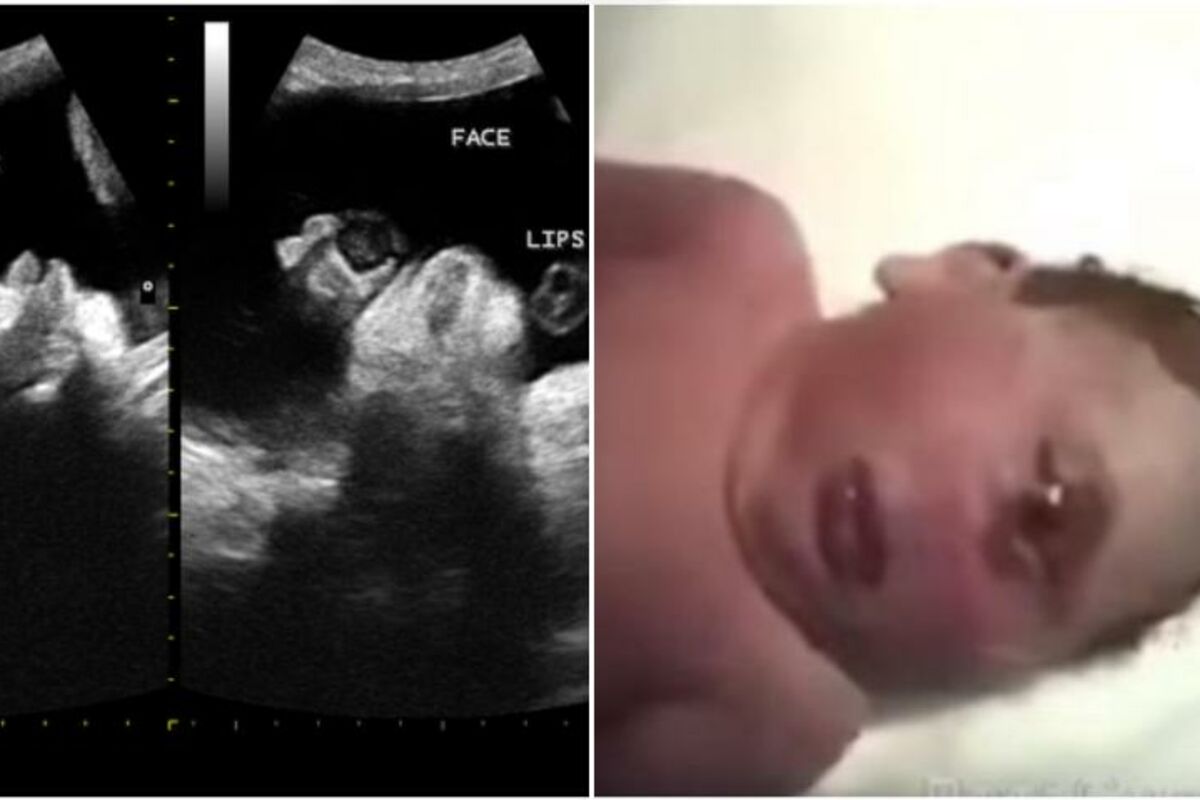

Danas se kiklopija može otkriti ultrazvučnim pregledom trudnice.

Kiklopiju spominju i u Američkom časopisu za medicinsku genetiku (American Journal of Medical Genetics). Opisali su slučaj kiklopije dijagnostikovane kod dva fetusa koja su imala i neke druge malformacije. Kada su se deca rodila, njihove sumnje bile su, nažalost, potvrđene.

Bila je to prva beba u toj porodici, a da s njom nešto nije u redu saznali su na ultrazvuku u ranoj trudnoći. Nesrećno dete je imalo jedno oko, nos mu je nedostajao, imalo je nekoliko deformacija na abdomenu i još neke nepravilnosti u razvoju. Živelo je svega pet sati.